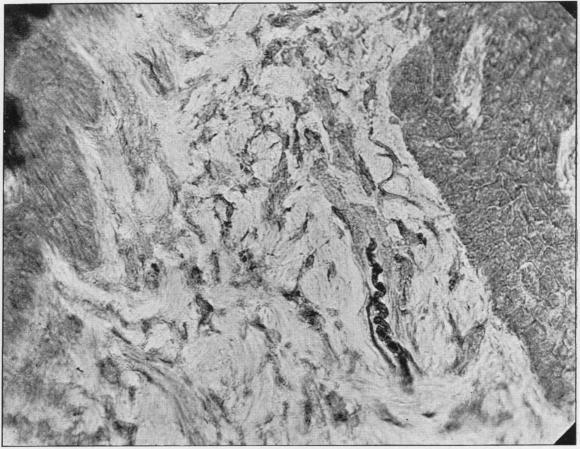

In this paper we give a comparative study of the innervation of the connective tissues of the gum underlying the epithelium. Our material was taken from carnivores, rodents, insectivores and men. The fibres form superficial and deep plexuses and leashes, and specialized nerve-endings are also present. The types of specialized nerve-endings seen have been:-(1) Coils which are situated either in the intra-papillary zone of the deeper connective tissue.(2) Ruffini-like nerve-endings and convoluted fibres the presence of which in the gum has not been previously described.

在本文中,我们对上皮下牙龈结缔组织的神经支配进行了比较研究。我们的材料取自食肉动物、啮齿动物、食虫动物和人类。纤维形成浅丛和深丛以及神经束,并且也存在特化的神经末梢。所见到的特化神经末梢类型有:(1)位于较深层结缔组织乳头内区的螺旋;(2)类鲁菲尼神经末梢和盘绕纤维,牙龈中它们的存在此前未曾有过描述。